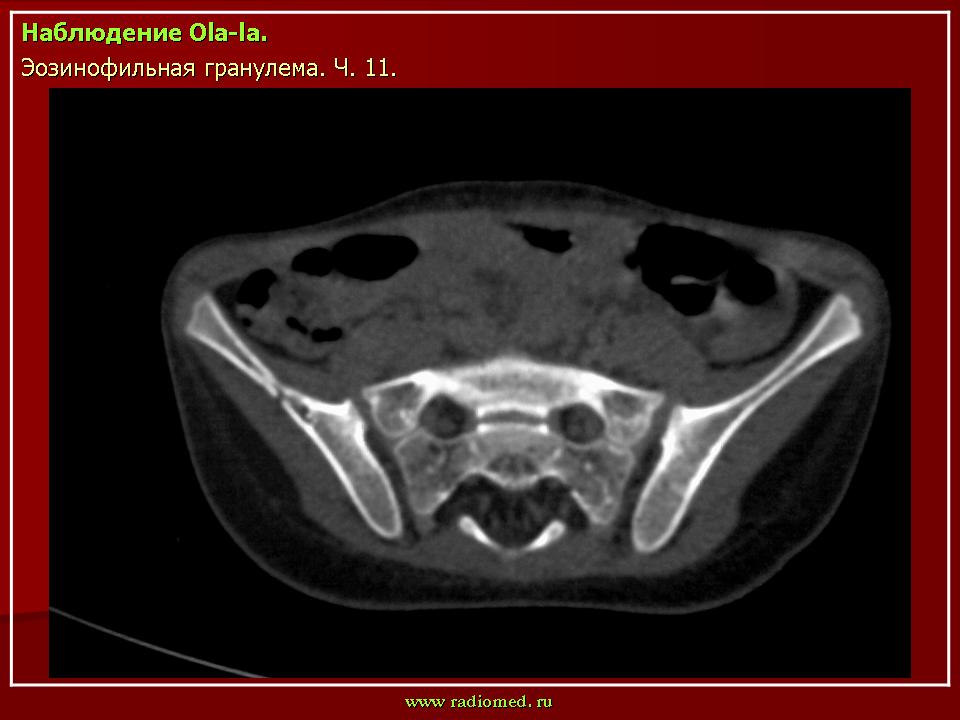

Продолжение.

Литическая деструкция левой подвздошной кости (стрелка).

Тело позвонка является наиболее часто поражающейся частью позвоночника. Ранние поражения проявляются, как литические очаги.

Формируется «VERTEBRA PLANA», что может привести к боли и значительным неврологическим расстройствам.